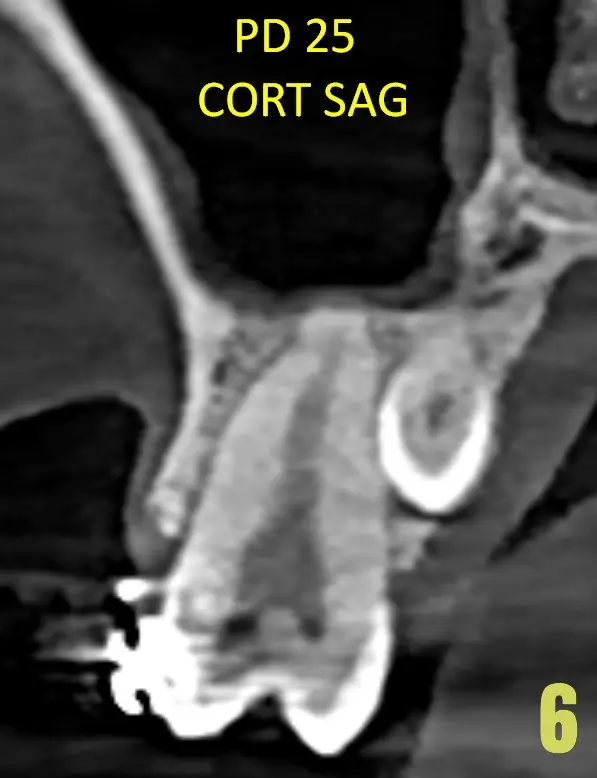

También logramos observar pieza dental supernumeraria en zona de pieza dental 25, también hacia palatino. (Imagen 06)